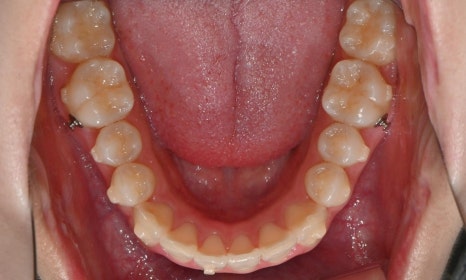

2025.3. 초진 (앞니 경미한 총생과 과개교합) - 연세정원치과

정밀진단 결과 위아래 앞니가 약간 겹쳐 있어 배열이 고르지 않은 상태였으며, 약간의 과개교합이 동반된 상태였습니다. 다만 골격적인 문제나 안모 불균형은 없었고, 측면에서도 돌출감 없이 비교적 안정적인 안모를 유지하고 있었습니다.

이러한 점을 종합적으로 고려해보았을 때 치아 배열의 개선과 교합 조정을 중심으로 한 비발치 교정 치료가 적합한 케이스였습니다. 또한 환자가 고등학생이라는 점, 그리고 학업과 일상 생활에 대한 부담을 최소화하고 싶다는 보호자의 의견을 반영하여, 인비절라인으로 선택하게 되었습니다.

이번 케이스는 인비절라인 Comprehensive로 치료를 진행하였으며, 치아 이동은 과도하지 않게 단계적으로 진행하기 위해 치간삭제를 최소한으로 적용하며 공간을 확보하는 방향으로, 총 33단계의 장치를 통해 치아 이동을 계획하였습니다.